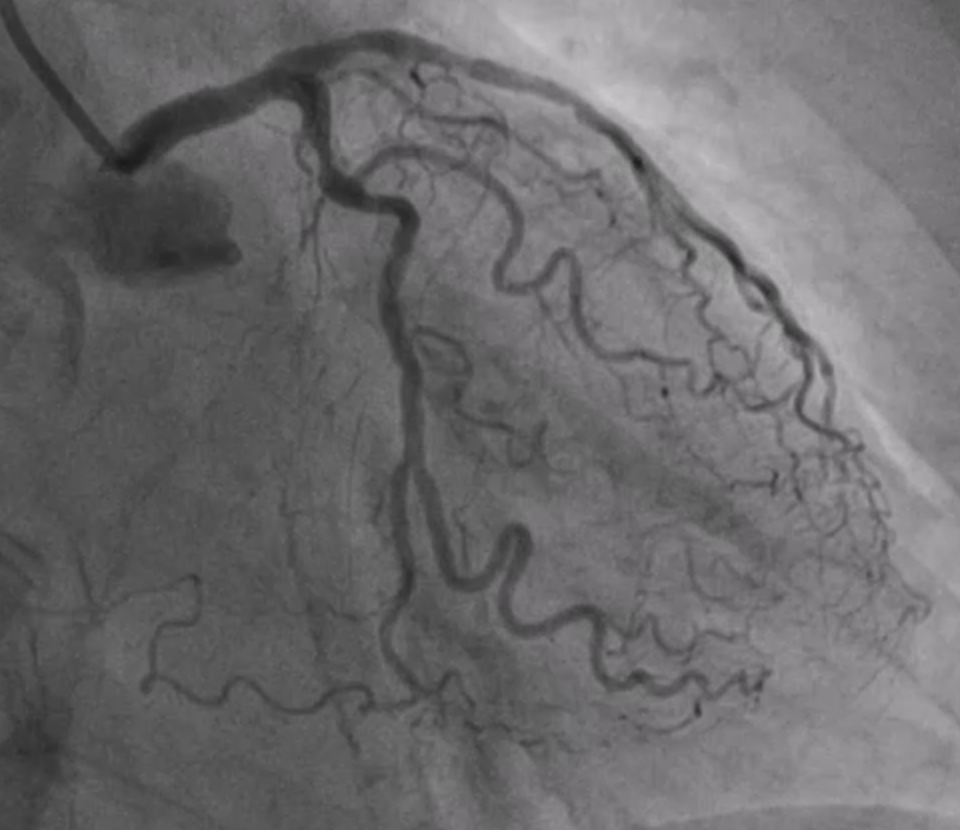

The coronary angiogram, performed via right radial access, revealed a mid-LAD chronic total occlusion (CTO), moderate stenosis in the proximal LCX, and critical stenosis in the mid-RCA. The RCA flow was TIMI 2. We decided to perform PCI on the RCA using the same access route.